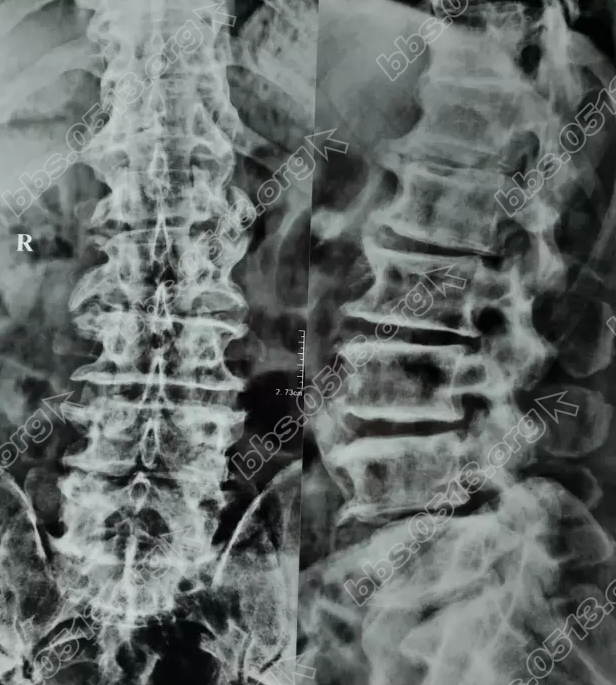

1.png

" Y' X0 V, G1 K% s$ H  入院后,我院医生就给丁大爷做了详细的检查,根据腰椎摄片、MRI检查以及详细的询问和查体后,可以诊断为“腰椎管狭窄症 、 腰椎滑脱症 、腰椎间盘突出症 、腰椎退变”。根据丁大爷的这一症状,已经严重影响到了生活,我院医生一致认为保守治疗无效,应该采取手术治疗。但由于患者年龄大,还有高血压、慢性心功能不全、脑多发性梗塞等病史,手术风险高,需要完善相关检查,综合评估后再定下一步治疗方案。/ T3 h/ N7 C; }0 R( d9 L3 h$ }& K

胡玉华院长说:因为手术治疗是腰椎间盘突出最后的治疗手段,不到万一得以都不推荐选择。手术治疗适合于因腰椎间盘突出引起无法行走,或行走严重受限的患者,比如像丁大爷,已经逐步出现行走障碍,并且腰椎前凸增加,腰椎活动度明显受限,推旁肌痉挛,L4棘突及其上下人带有压痛,呈台阶状。因此我们给予患者手术治疗。2 t$ C/ u3 A) h